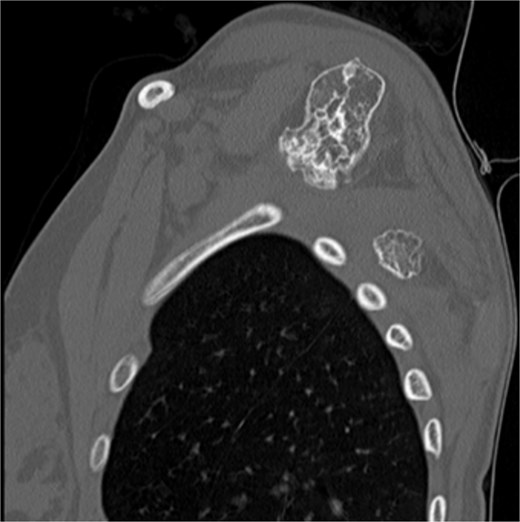

The imaging investigation was initiated by our department, as we were clinically suspicious of the presence of osteochondromas, due to the history of HME in both patients. Both patients were subscribed an anteroposterior X-ray of left shoulder and a CT scan for pre-operative planning. Also, radiographic evaluation of both knees and left forearm were taken and revealed multiple exostoses as a part of the HME follow-up that both girls underwent. The CT scan of the 14 year old patient demonstrated three bony lesions arising from the ventral aspect of left scapula. The largest one extruded from superior angle heading medially to the vertebral bodies. The other two smaller arose one from the lateral angle and one from the inferior angle. The CT scan of the 9 year old patient revealed one bony lesion arising ventrally from the superior angle of the left scapula heading medially as well (Figs 2 and 3). The diagnosis of VSO was made in both cases.

CT of the 14-year-old patient showing the largest lesion arising ventrally from the superior angle of left scapula in axial plane.